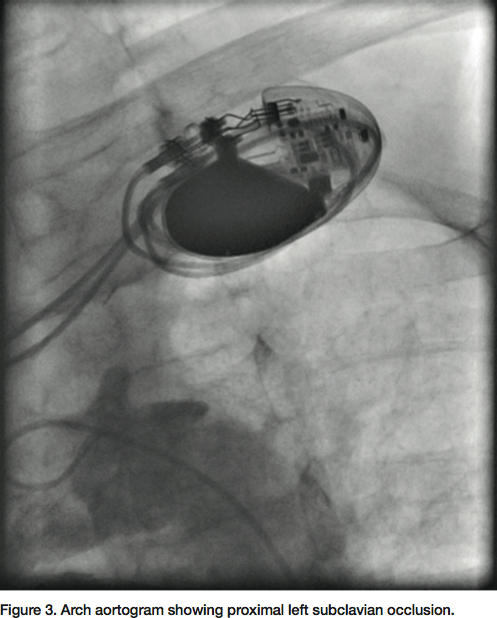

sheath. Severe native coronary artery disease was noted, with 100% occlusion of the LAD, left circumflex (LCX) and right coronary artery (RCA). The SVG to OM and SVG to RCA grafts were widely patent, with good runoff. The arch aortogram showed a very proximal 100% left subclavian artery occlusion (Figure 3). Percutaneous intervention of the left subclavian occlusion was performed to treat the lifestyle-limiting angina from coronary steal during the use of the left upper limb. From the radial access, a 0.018” Astato wire with a 30-

- If there is occlusive disease, contralateral radial access or a 4 French femoral access can be used to perform an arch aortogram (Figure 3). To cross an occlusion, consider using a JR 4 catheter, Bernstein catheter (Boston Scientific), or an angled or straight crossing catheter in conjunction with a 0.014” or 0.018” CTO wire, per the operator’s discretion. An intraluminal course can be guided by placing a catheter from the other access. After crossing the occlusion, the intraluminal position should be confirmed. If required, a re-entry device like the Outback (Cordis), Pioneer (Medtronic) or Enteer (Covidien) can be used, as per the operator’s experience. It is relatively easy to advance these devices from the radial access to the point of disease.